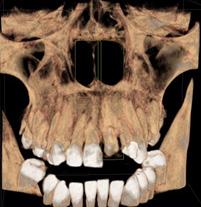

Protocolo Odontológico Quirúrgico Aplicado a Pacientes con VIH+: A propósito de un caso clínico

Reporte de Caso

Surgical Dental Protocol Applied to Patients with HIV

+: About a clinical case

Javier Boris Adrián Burgos

Nathalie Andrea Candia López

Noelia Vargas Ovando